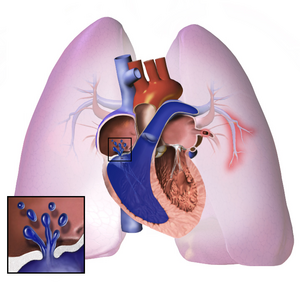

| فرط ضغط الدم الرئوي. | |

فرط ضغط الدم الرئوي Pulmonary Hypertension، هو زيادة ضغط الدم داخل الشريان الرئوي أو الوريد الرئوي أو الشعيرات الدموية الرئوية (جميعها تعرف بالأوعية الرئوية أو أوعية الدورة الدموية الصغرى)، وزيادة الضغط في هذه الأوعية يؤدي إلى ظهور بعض الأعراض كضيق النّفس، الدوار، الاغماء، تورّم القدم والعديد من الأعراض الأخرى، التي تتفاقم جميعها مع ازدياد المجهود الجسدي. من الممكن أن يكون فرط ضغط الدّم الرئوي شديد جداً، مما يؤدي إلى قلة تحمل الجسم للتمارين الرياضيّة، تماماً كما يحدث في حالات الفشل القلبي.

الإصابة

أياً كان السبب الرئيسي للمرض، إنّ فرط ضغط الدم الرئوي الشرياني (الذي يصنف ضمن مجموعة منظمة الصحة العالمية الأولى) يحدث بسبب تضيق الأوعية الدموية الموجودة داخل الرئتين. مما يصّعب على القلب ضخ الدم إلى الرئتين، تماماً كما يحدث في حالة ضخ الماء خلال أنبوبة ضيقة مقارنةً مع ضخه خلال أنبوبة واسعة. مع مرور الزمن فإن الأوعية الدموية المتضررة تصبح أكثر صلابة وغلاظة بسبب عملية تسمى التليف، مما يسبب لاحقاً زيادة في ضغط الدم داخل الرئة واعاقة لتدفق الدم خلالها. تشترك جميع انواع فرط ضغط الدم الرئوي بأن زيادة الجهد المبذول على القلب يؤدي إلى تضخم في عضلة البطين الأيمن مما يجعل القلب اقل قدرة على ضخ الدم إلى الرئتين مسبباً ما يعرف بالفشل القلبي الأيمن (فشل الجانب الأيمن من القلب) وتسمى هذه الحالة كور بالمونيلا. البطين الأيمن يكون عادةَ تحت تأثير نظام يعتمد على الضغط المنخفض، حيث يكون الضغط فيه جزء من ستة أجزاء الضغط الموجود في البطين الأيسر. ولهذا فان البطين الأيمن لا يستطيع التعامل مع ضغط بارتفاع ذاك الموجود في البطين الأيسر، حتى مع ان تضخم عضلات البطين قد تساعده في بادئ الأمر، لكن مع مرور الزمن وزيادة التضخم فانه يصل إلى حالة لا تستطيع معها العضلات الحصول على الاوكسجين الكافي لعملها مما يؤدي إلى الفشل القلبي الأيمن. مع قلة تدفق الدم إلى الرئتين, يقل الدم المتدفق إلى البطين الايسر (لأن القلب اصبح يستقبل كمية أقل من الدم)، هذا الدم عادة يكون محمل بكمية اقل من الاوكسجين. مما يقلل من كمية الدم المنتقلة إلى باقي الجسم عبر الدورة الدموية الكبرى خاصةَ اثناء زيادة النشاطات البدنية.